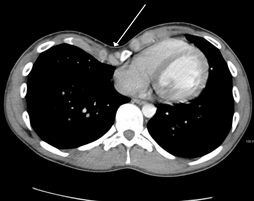

中国完成世界首例3D打印漏斗胸矫形手术